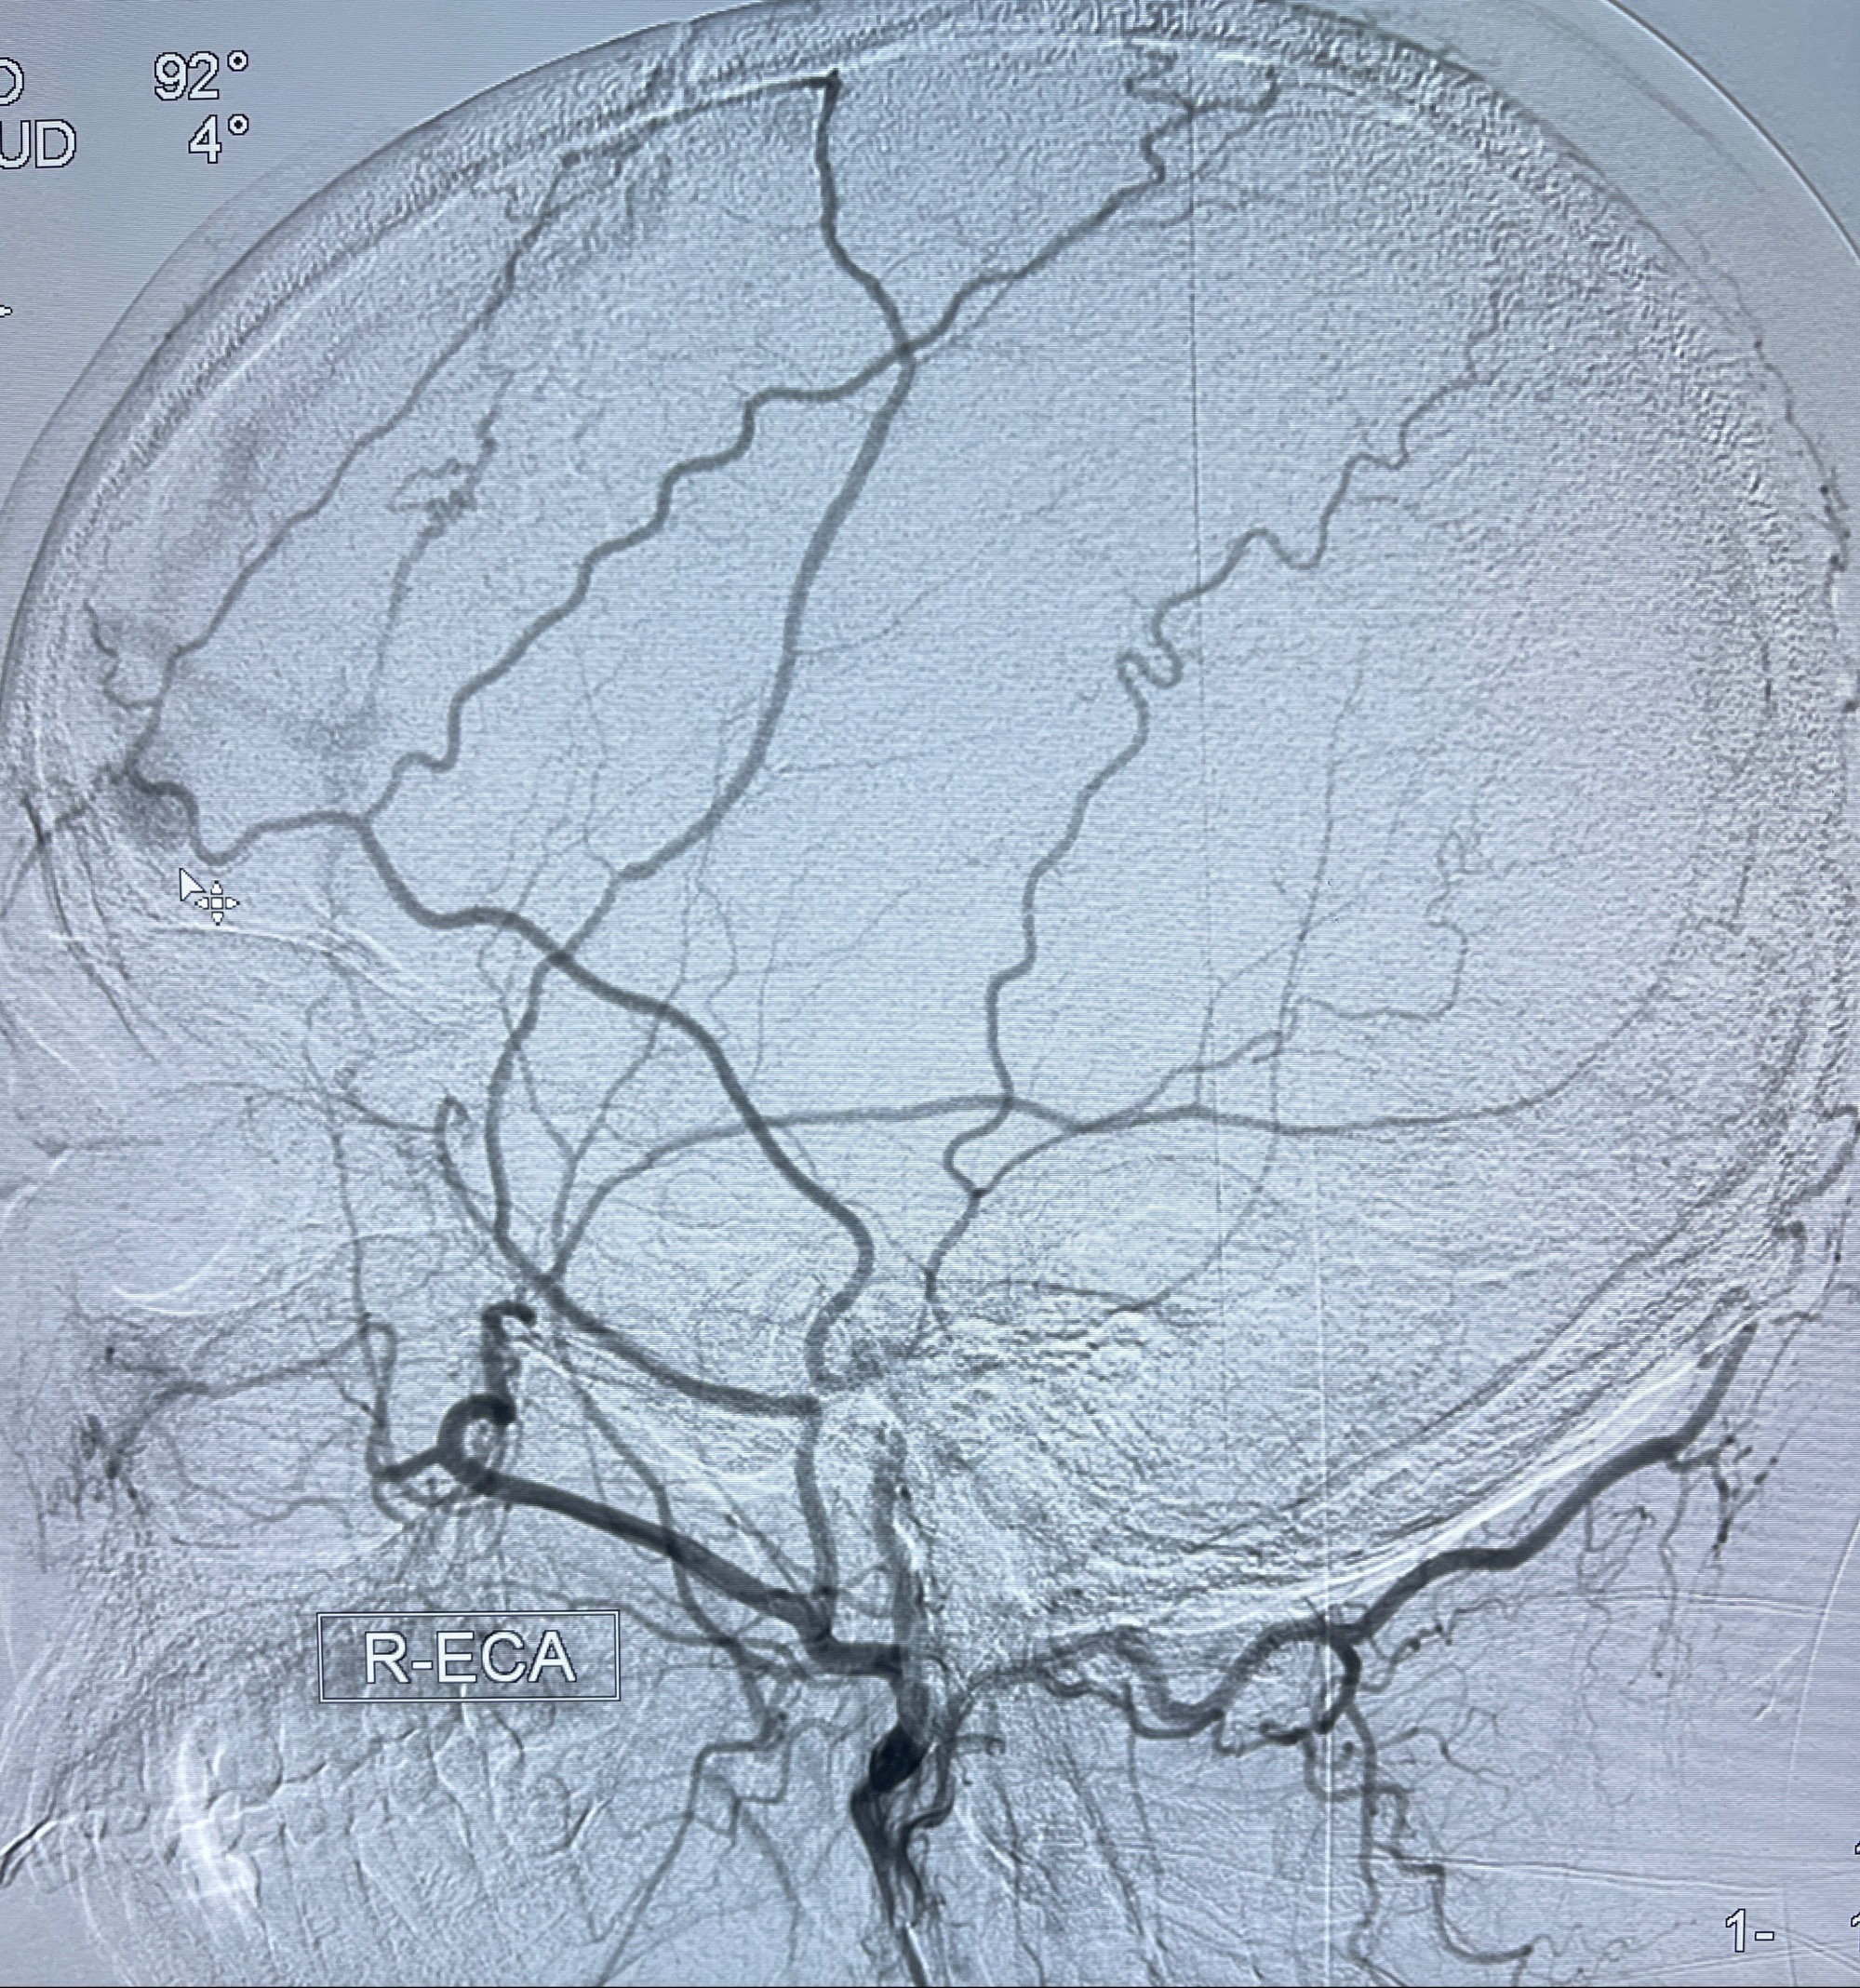

2023-09-13全脑血管造影:前颅底硬脑膜动静脉瘘,供血动脉为双侧胼周动脉、眼动脉脑膜支,静脉向上矢状窦方向引流